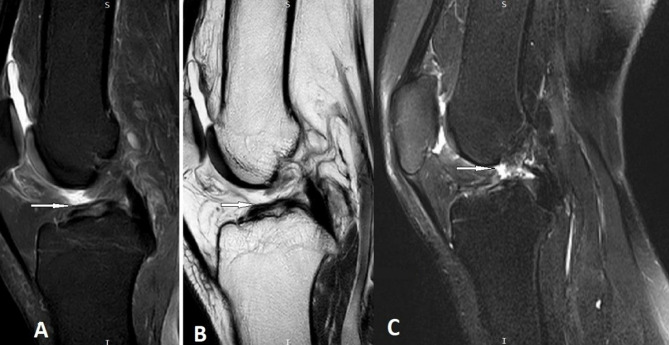

The Anterior Cruciate Ligament (ACL) is considered the most commonly injured ligament of the knee. Magnetic Resonance Imaging (MRI) has become an indispensable imaging tool and modality of choice for assessing and managing knee conditions. This article outlines an effective MRI imaging technique that improves the diagnostic accuracy of ACL injuries of the knee, covering the appropriate pulse sequences and optimal imaging planes. Furthermore, the article provides a comprehensive review of the appearance of complete and partial ACL tears on MRI in the acute and chronic phases. In addition, it identifies and illustrates the primary MRI signs (signs related to the absence or abnormal visualization of the ACL fibers) and secondary MRI signs (signs related to the mechanism of injury or associated knee injuries) of ACL injury.